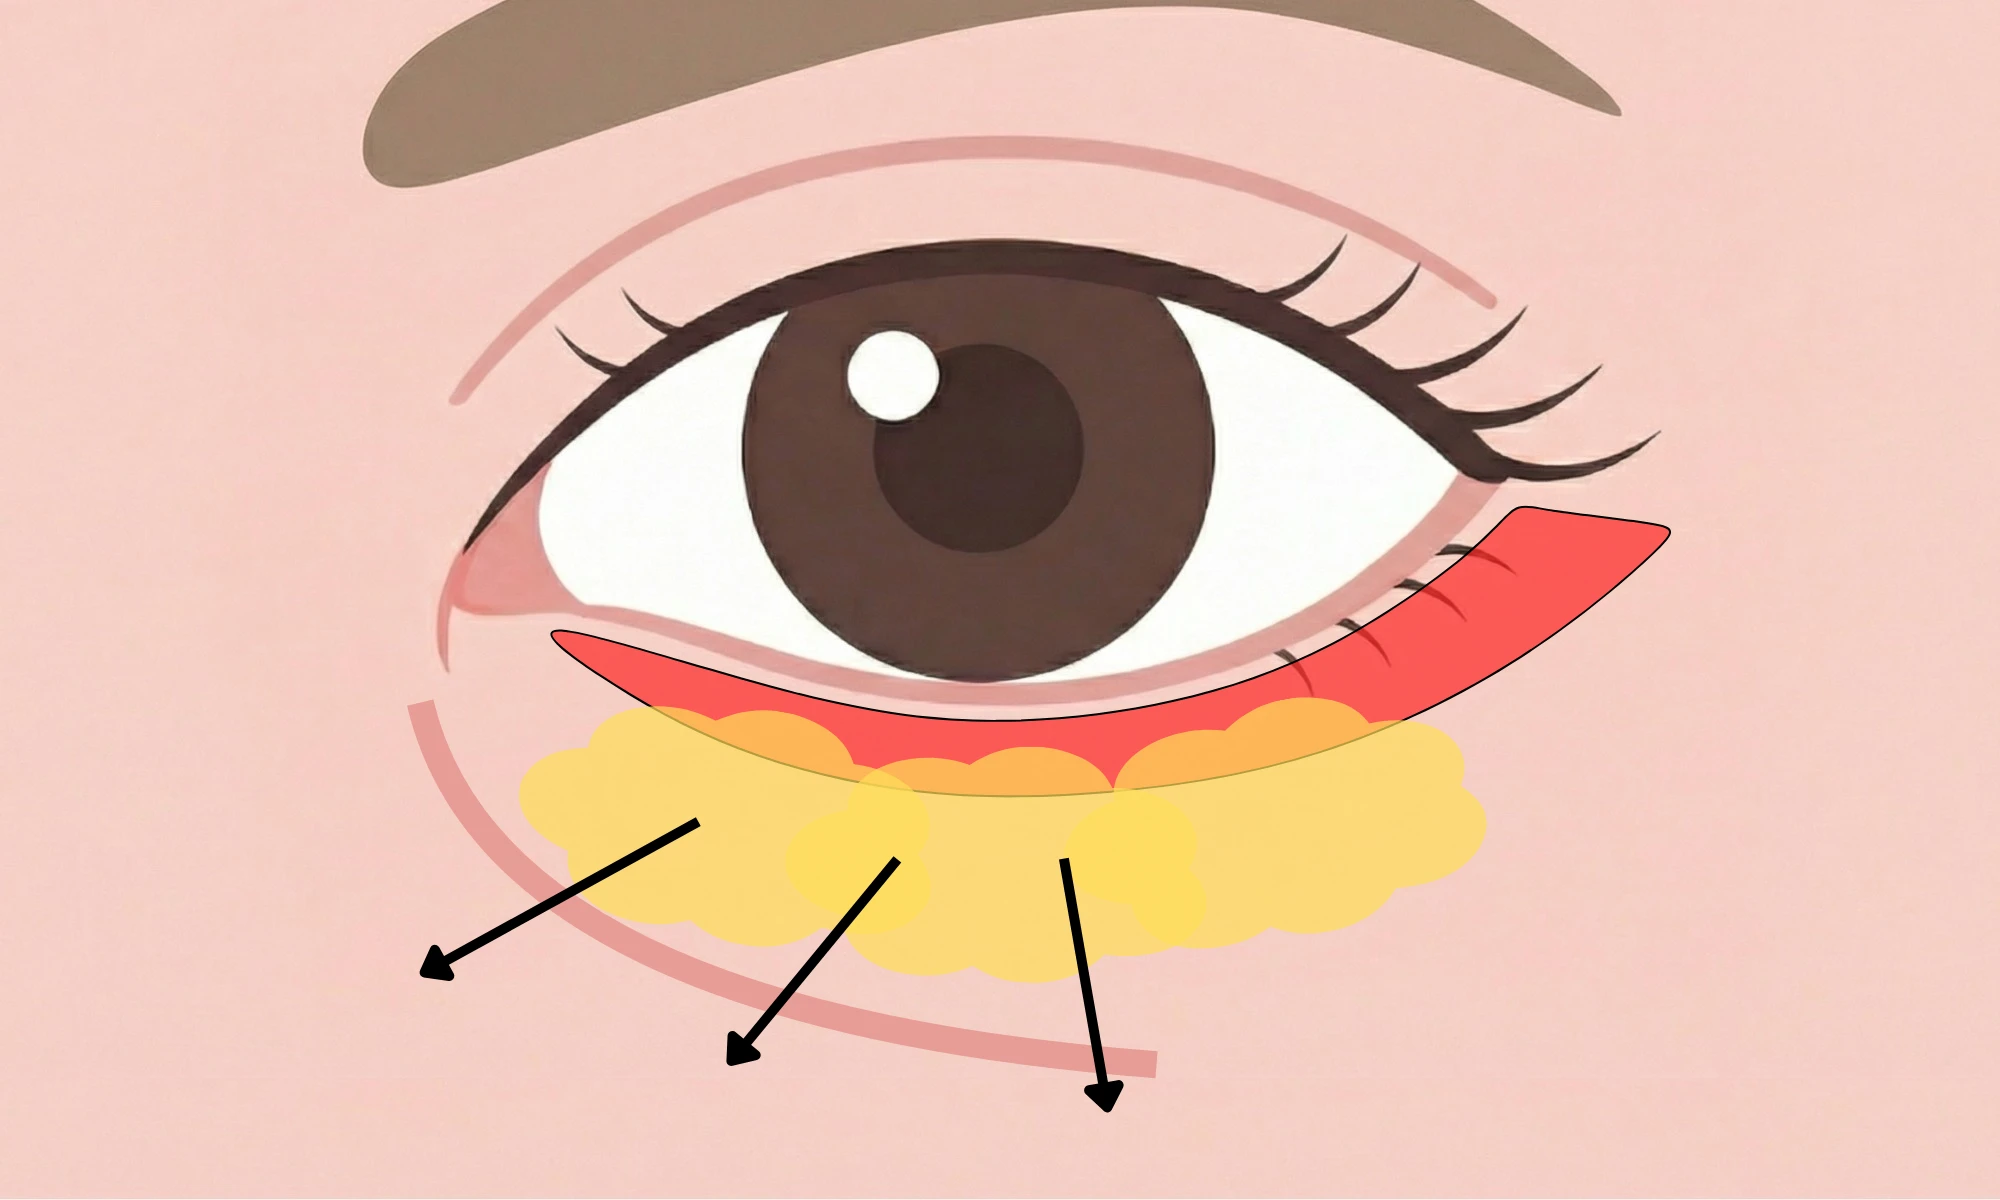

表ハムラ法とは、まつ毛の生え際部分から下まぶたの皮膚を切開し、

骨と皮膚を繋ぐ強い靭帯の解除し、眼窩脂肪の再配置、余剰皮膚切除を行う手術です。

表ハムラ法は、靭帯の癒着によるくぼみ、皮膚の余りによるたるみ、この両方が同時に存在するケースに対応できる治療です。

脂肪を再配置してくぼみをなだらかに整え、余剰皮膚を切除し、さらに緩んだ眼輪筋を適切に引き締めて固定することで、

下まぶたの構造全体を立体的に再設計します。

裏ハムラ法と同様に、表ハムラ法でも、くぼみの原因となる靭帯の癒着を丁寧に解除します。

そのうえで、眼窩脂肪を前方へ再配置することで、再癒着を防ぎながら、

眼窩縁〜ティアトラフ(目頭側)の食い込みや段差をなだらかに整えます。